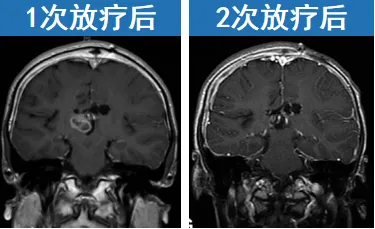

手术仅是治疗的基础环节。为控制肿瘤进展,Rutka教授为肖恩制定了局部放疗方案。经过2次放疗后,随访显示病情得到有效控制。患儿实现6年无病生存,顺利进入成年期,期间未出现肿瘤复发。